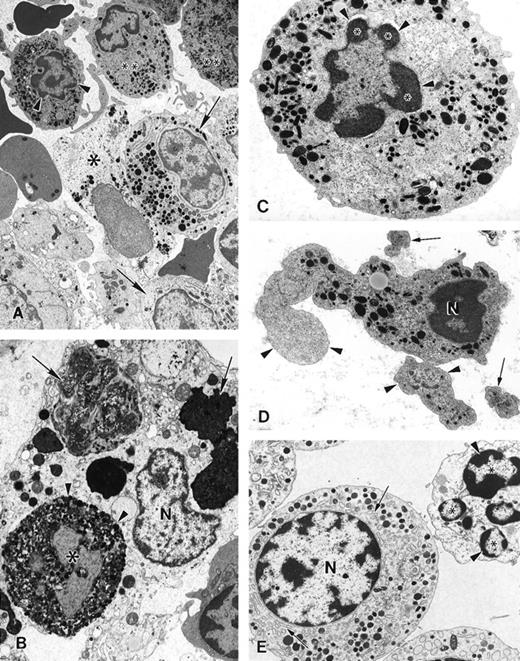

Electron microscopy of bone marrow cells in myelokathexis

The ultrastructure of bone marrow cells from patient 2 and a healthy volunteer donor was investigated before and during G-CSF therapy using electron microscopy (Figure 4). The bone marrow aspirate from a healthy volunteer contained predominantly neutrophils at various stages of maturation and immature red blood cells (Figure 4A; arrowheads). Few degenerating cells and minimal cellular debris were observed. In contrast, numerous degenerating cells (indicated by arrows) were present in the bone marrow aspirate from a patient with myelokathexis. In the degenerating cells, typical features of apoptosis were present, including the convoluted nucleus in an otherwise still intact cell. The granules (G) were aggregated, and the heterochromatin was concentrated in distinct, dense granular patches located on the inner surface of the nuclear membrane (Figure 4B). At higher magnification, apoptotic features such as cytoplasmic blebbing (arrowheads) and intense condensation of chromatin in the nucleus (N) were readily apparent in neutrophils (Figure 4). Macrophages were observed with numerous phagosomes that contained cellular debris as a result of phagocytizing senescent cells (Figure 4D). These apoptotic features were not present in the bone marrow aspirate from a healthy volunteer. These data indicated that accelerated apoptosis occurs in vivo in the myeloid precursor population in patients with myelokathexis.

Electron micrographs of bone marrow from patient 2 before granulocyte colony-stimulating factor treatment.

(A) Low magnification of the bone marrow shows degenerating cells (*), few mature neutrophils (**), and promyelocytes (arrows). Neutrophils with convoluted nuclei (arrowheads), a sign of early apoptosis, are observed. Magnification ×4000. (B) Macrophage in the bone marrow contains several phagosomes (arrows) with cellular debris of neutrophils. Neutrophil (arrowheads) with a distinguishable nucleus (*) and granules is discernible in 1 of the phagosomes. N, macrophage nucleus. Magnification ×6500. (C) Neutrophil in an early stage of apoptosis. The nucleus is convoluted (arrowheads), and the chromatin is condensed and distinctly circumscribed, forming dense granular masses (*) along the inner surface of the nuclear envelope. Magnification ×7500. (D) Neutrophil in a later stage of apoptosis. The cell shows cytoplasmic blebbing (arrowheads) and cellular fragmentation (arrow). N, nucleus. Magnification ×13,000. (E) Promyelocytes observed in the bone marrow. The cell at the bottom left appears normal and has a large, round nucleus (N), numerous granules, and a well-developed rough endoplasmic reticulum (arrows). The cell at the top right is apoptotic, as indicated by the fragmented nucleus (*), and has distinct areas of condensed chromatin (arrowheads). Magnification ×5500.

Electron micrographs of bone marrow from patient 2 before granulocyte colony-stimulating factor treatment.

(A) Low magnification of the bone marrow shows degenerating cells (*), few mature neutrophils (**), and promyelocytes (arrows). Neutrophils with convoluted nuclei (arrowheads), a sign of early apoptosis, are observed. Magnification ×4000. (B) Macrophage in the bone marrow contains several phagosomes (arrows) with cellular debris of neutrophils. Neutrophil (arrowheads) with a distinguishable nucleus (*) and granules is discernible in 1 of the phagosomes. N, macrophage nucleus. Magnification ×6500. (C) Neutrophil in an early stage of apoptosis. The nucleus is convoluted (arrowheads), and the chromatin is condensed and distinctly circumscribed, forming dense granular masses (*) along the inner surface of the nuclear envelope. Magnification ×7500. (D) Neutrophil in a later stage of apoptosis. The cell shows cytoplasmic blebbing (arrowheads) and cellular fragmentation (arrow). N, nucleus. Magnification ×13,000. (E) Promyelocytes observed in the bone marrow. The cell at the bottom left appears normal and has a large, round nucleus (N), numerous granules, and a well-developed rough endoplasmic reticulum (arrows). The cell at the top right is apoptotic, as indicated by the fragmented nucleus (*), and has distinct areas of condensed chromatin (arrowheads). Magnification ×5500.

To investigate the cellular and molecular defects responsible for ineffective granulocytopenia in myelokathexis, we studied 4 patients from 2 unrelated families. The morphologic appearance of bone marrow-derived cells from these patients, as determined by light and electron microscopy, demonstrated that mature marrow and blood neutrophils, as well as myeloid-committed precursors, underwent degenerative changes that were characterized by profound apoptotic features, including extended cytoplasmic membrane blebbing, granule aggregation, cytoplasmic vacuolization, and intensive condensation of heterochromatin in the nucleus (Figure 4). Such apoptotic cells became hypofunctional and were removed from the intramedullary space by bone marrow macrophages through phagocytosis (Figure 4).